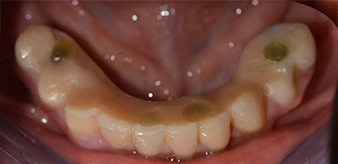

Nach der Aufklärung über die verschiedenen Möglichkeiten der Versorgung entschied sich die Patientin für eine Extraktion der Restbezahnung im Unterkiefer, eine Sofortimplantation und Versorgung mit der sogenannten Fast & Fixed-Methode (bredent medical). Hierbei wird der provisorische festsitzende Zahnersatz bereits am OP-Tag auf vier Implantaten verschraubt. Das Ziel war, die Patientin am Freitag zu operieren, sodass sie am Montag darauf an den mündlichen Abiturprüfungen teilnehmen konnte.

Zur Planung und Risikominimierung wurde eine dreidimensionale Volumentomografie (DVT, Planmeca) erstellt. Dieses zeigte, dass die Qualität und Quantität des Knochens für eine Operation und Sofortversorgung nach der Fast & Fixed-Methode ausreichend war. Nach Protokoll dieses Konzeptes wird in Regio 35, 32, 42 und 45 implantiert. Durch die bis zu 45-Grad-Schiefstellung der distalen Implantate wird das Durchtrittsprofil nach posterior verlegt und ein größeres Stützpolygon erreicht (Abb. 3).